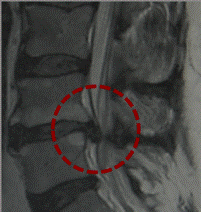

Se realizaran analíticas generales y específicas para descartar procesos artríticos o reumáticos, complementándolas con Radiografías Simples aunque en la actualidad resonancia magnética (RM) nos aporta una gran información, que nos permite hacer un diagnóstico certero sobre la patología, por ejemplo: hernias discales, protrusiones, estenosis del canal, discopatía, síndrome facetario y otras anomalías. Aunque este examen esta contraindicado para pacientes que tengan implantado marcapasos, implantes coclear, estimulador nervioso, clic de aneurisma cerebral, fragmentos metálicos intraoculares, cuerpos extraños ferromagnéticos, presencia de algún material desconocido, claustrofobia.

En estos casos podremos hacer uso de la Tomografía Computarizada (TC) que nos permite valorar fracturas, tumoraciones, metástasis, entre otros. La gammagrafía ósea, es otra de las pruebas que nos permite saber si hay actividad ósea ya sea, tumoraciones, metástasis y procesos inflamatorios. La Electromiografía, es un estudio de la velocidad de conducción del nervio, nos indica si la raíz que se encuentra afectada y si existe compresión de la misma.